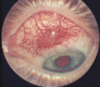

2

pt is slumped over from severe eye pain, and has vision loss. Complains of headache, nausea, and vomiting and see light halos. See conjunctival redness (ciliary flush) and poorly reactive dilated pupil or mid dilation fixed pupil. No discharge.

acute angle closure glucoma call opthalmology- optic atrophy and permanent vision loss can occur in a few hours without tx. If unable to see eye doctor within hour try to treat with topical pilocarpine and other intraocular pressure lowering agents (Timolol or apraclonidine) Precipitated by exposure to sympathomimetic and anticholinergic drugs. Seen more in Asian people.